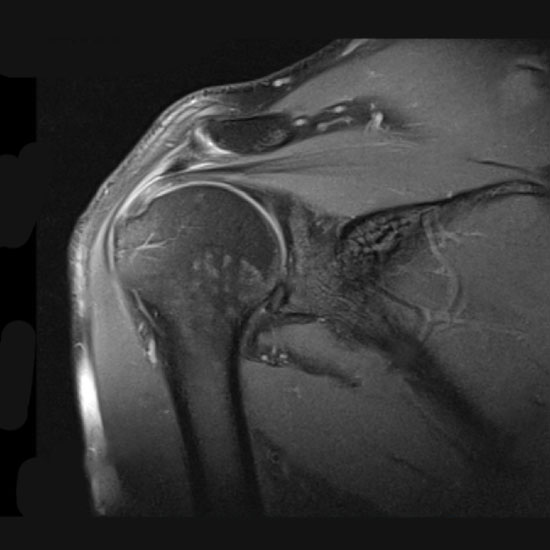

An MRI Both Shoulder Joint scan is an imaging procedure that is used to visualize the blood vessels, bones, and tissues in the shoulder region. The doctor recommends for shoulder MRI scan to assess the problems in the shoulder joint and its surrounding tissues. Various problems/conditions affect the shoulder joint and cause wear and tear to the joint.